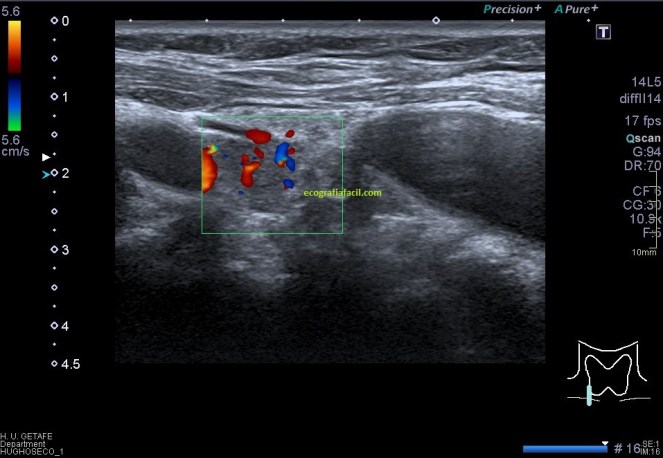

Ahora queda ver cómo es su vascularización.

La vascularización no aporta demasiado, no suele ser concluyente, excepto en pacientes infantes, donde las lesiones pueden ser muy sutiles, aquí sí. Puedes ver en la imagen 6 que la vascularización afecta de modo similar tanto a la parte afectada por el tumor testicular, tanto como en la parte sana.